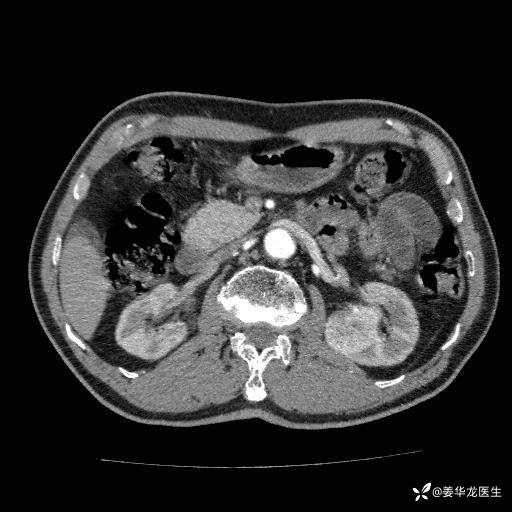

左肾中心型肾门部肿瘤39mm×34mm×36mm,右肾GFR25ml/min,部分切还是全切?

患者75岁老年男性,体重50kg,无高血压、肾病、糖尿病等基础病,检查发现左肾中心型肾门部肿瘤,右肾GFR只有25ml,无肉眼血尿,无镜下血尿。入院验血常规检查均正常,包括肾功能,肌酐102.7umol/L.

二、左肾肿瘤与左肾集合系、左肾动静脉关系密切,左肾部分切除术可行吗?成功率有多大?成功部分切后,肾功能还有多少?